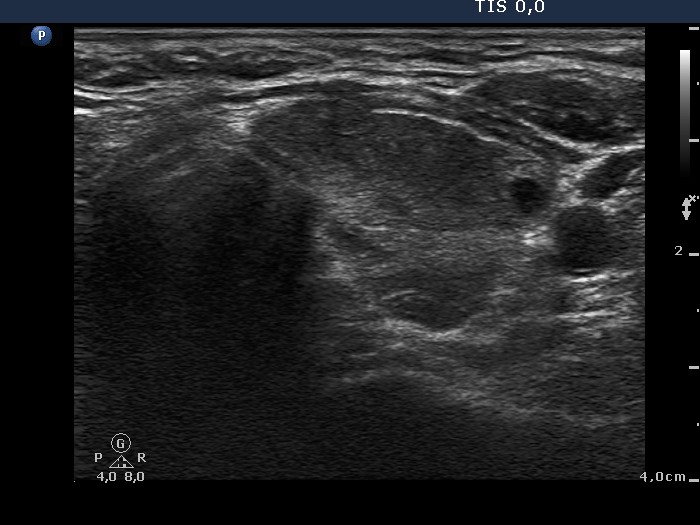

First examination (first row):

Clinical presentation: A 28-year-old woman was referred for evaluation of a recurrent hyperthyroidism. She underwent radioiodine therapy 3 years ago. She did not require replacement therapy and was euthyroid in the previous 30 months. Her original complaints recurred for two months, including 8 kg loss in weight and tachycardia.

Palpation: Both thyroids were enlarged and moderately firm.

Result of blood test: hyperthyroidism (TSH undetectable, FT4 38.6 pM/L).

Ultrasonography: A diffusely hypoechogenic thyroid was found with multiple more hypoechogenic lesions. None of them corresponded to a nodule. The vascularization was increased.Daily 20 mg methimazole was administered and repeat radioiodine therapy was advised after reaching the euthyroid state.